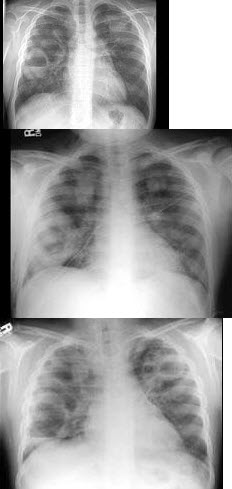

126、单项选择题

女,出生2天,呼吸困难、发绀,结合图像,最可能的诊断是()

A.呼吸窘迫综合征

B.新生儿肺炎

C.法洛四联征

D.新生儿支气管炎

E.胎粪吸入综合征